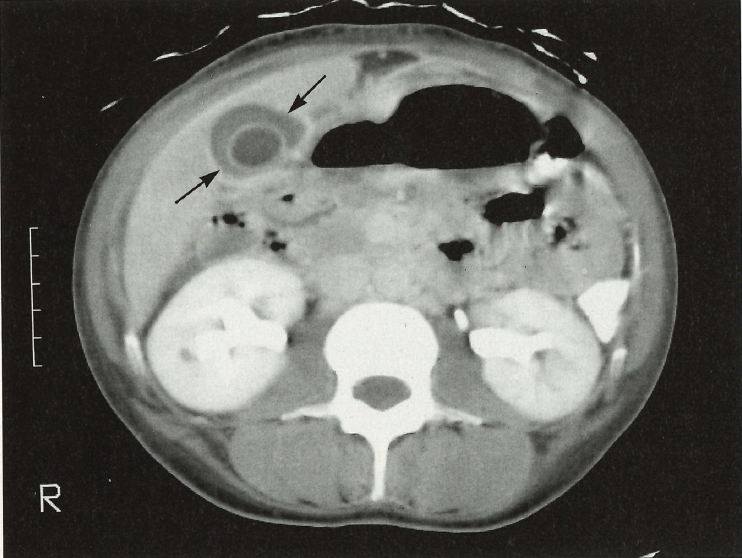

Approximately 10% of all cases of gallbladder inflammation are caused by acute acalculous cholecystitis.